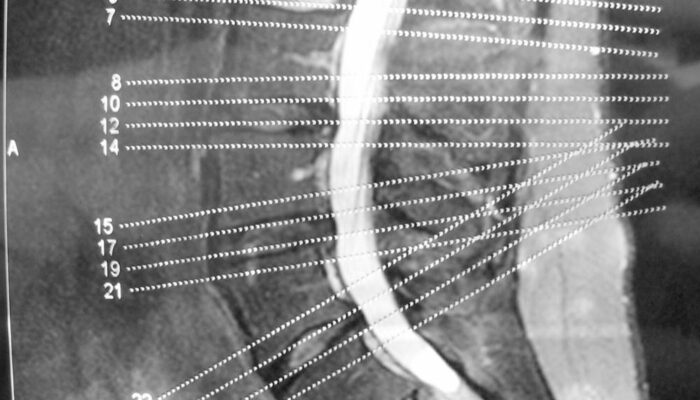

The spinal column consists of spinal discs that perform the task of providing padding between the vertebrae, i.e., the series of small bones that make up our backbone. They also act as shock absorbers and help the back remain flexible. As we age, these discs start gradually losing their elasticity property.

A common cause of this condition is the drying of your spinal discs. As you age, the water in the spinal discs dries out, flattening the spinal disc. A flattened spinal disc cannot absorb shock and they fail to provide padding to the vertebrae. Another cause of this disease can be a crack in the spinal disc. If the walls of the disc tear out, then there is a high chance that the soft core of the disc might push through the cracks and cause the disc to swell or, in the worst case, slip off.

This disease affects the facet joints, which are the joints that protect the vertebra in the spinal column from both sides. These joints make it possible for the spine to bend effortlessly.

The facet joints are lined with cartilages that cushion the joint and make sure that two adjacent vertebrae can glide smoothly against one another.